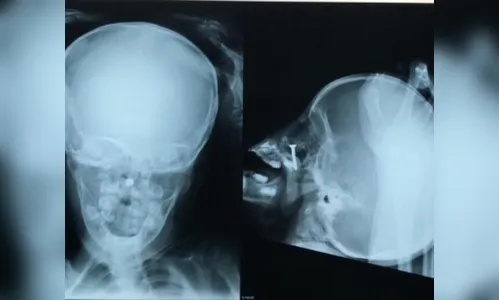

“Ela enfiou um parafuso dentro do nariz, a criança quando chegou estava muito agitada, tivemos que fazer uma radiografia para ver onde exatamente o objeto estava. Teve que ser feito um procedimento cirúrgico nela com anestesia geral. Ela foi intubada, porque, como é muito pequena, havia o risco de o parafuso machucar e ter sangramento, caso ela se mexesse. Então, optamos por esse procedimento por vídeo.”

Foram, no total, três médicos que participaram da cirurgia, sendo dois otorrinos e um anestesiologista. “Quando estávamos fazendo o procedimento o objeto foi para a parte de trás e caiu na boca, então, retiramos. Não teve nenhuma complicação, pois o parafuso não chegou a ficar muito tempo dentro do nariz, não deu tempo infeccionar. ”